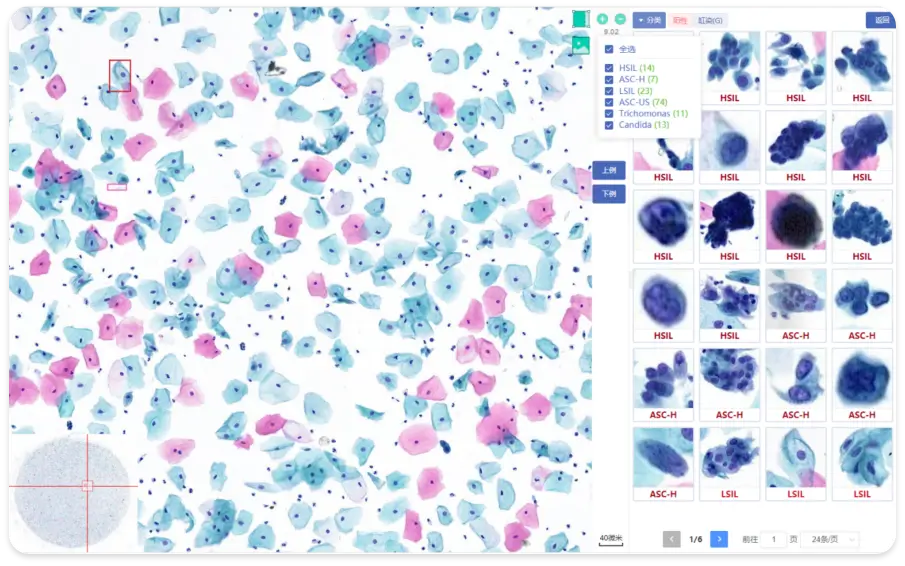

AI-powered Cervical Cancer Screening Solution

AI-powered cervical cancer screening integrated solution includes AI reagents, staining and production equipment, AI-powered initial

diagnosis, and digital slides storage solutions. KFBIO customizes the optimal solutions for customers to meet different needs.

Feature Highlights

One system complete 1500 cases per day

Standard business management of AI cervical cancer screening

Standardized AI cervical cancer screening business management

Whole workflow quality control of intelligent cervical cancer screening

Continuous track of positive cases and one-click consultation for difficult cases

Identification Pattern

1. Normal tissue

2. Low & High grade

intraepithelial neoplasia

3. Adenocarcinoma

Artificial intelligence is applied based on Deep Convolutional Neural Networkd (DCNN) to retrospectively

analyze cervical liquid-based cytology samples to confirm its feasibility in clinical practice.

Whole-slide images annotation,

suspected cell detection model training

Efficient method to detect suspicious

cells in WSI, validate model with a large

number of slides

High sensitivity validated in clinical

practice for different lesion types

Graded lesion cells, count cell quantity

automatically

Whole-slide analysis, high TPR, slide

quality intelligent assessment

Built-in error correction feedback system,

periodically update algorithm

B/S architecture, convenient access,

strong scalability

Support local and cloud deployment